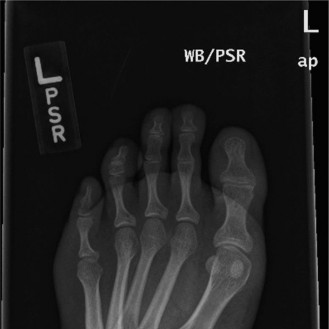

A 22-year-old female presents complaining of pain along the lateral border of her left foot. She has a known history of Charcot–Marie–Tooth disease (CMT) and a clinically evident pes cavus. Radiographs are obtained (Figs. 5–47 and 5–48).

Figure 5–47 Lateral weight-bearing radiograph of the foot.

The correct answer is (D). Before any deformity-correcting surgery for pes cavus, one must first assess whether the hindfoot position is flexible or rigid. A hindfoot varus is deemed flexible when hindfoot alignment can be moved into more neutral position, either with passive testing of subtalar range of motion or with Coleman block testing. Flexible deformities progressively become rigid over time through degenerative changes in the affected joints. Once the subtalar joint is arthritic, the hindfoot varus can no longer be corrected through subtalar range of motion. In such cases, a corrective arthrodesis of the subtalar joint is necessary to correct hindfoot alignment.